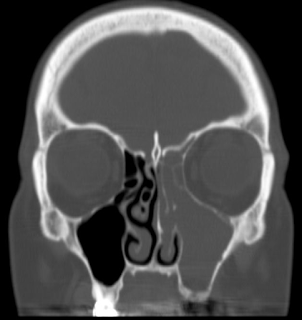

A 51 year old female presents with one year of left facial & tooth pain, left nasal obstruction, postnasal drainage and headaches. Past dental history is significant for RCT of teeth 10 & 11, apicoectomy of tooth #10, and dental implants #12 & 13. The implants failed and she developed an oral antral fistula after removal of the implants and debridement of necrotic bone. Coronal CT image demonstrating severe left maxillary and ethmoid sinus disease. This one sided sinus disease was of odontogenic origin.